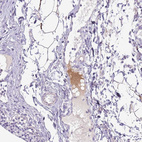

Immunohistochemical staining of human rectum shows strong positivity in plasma.